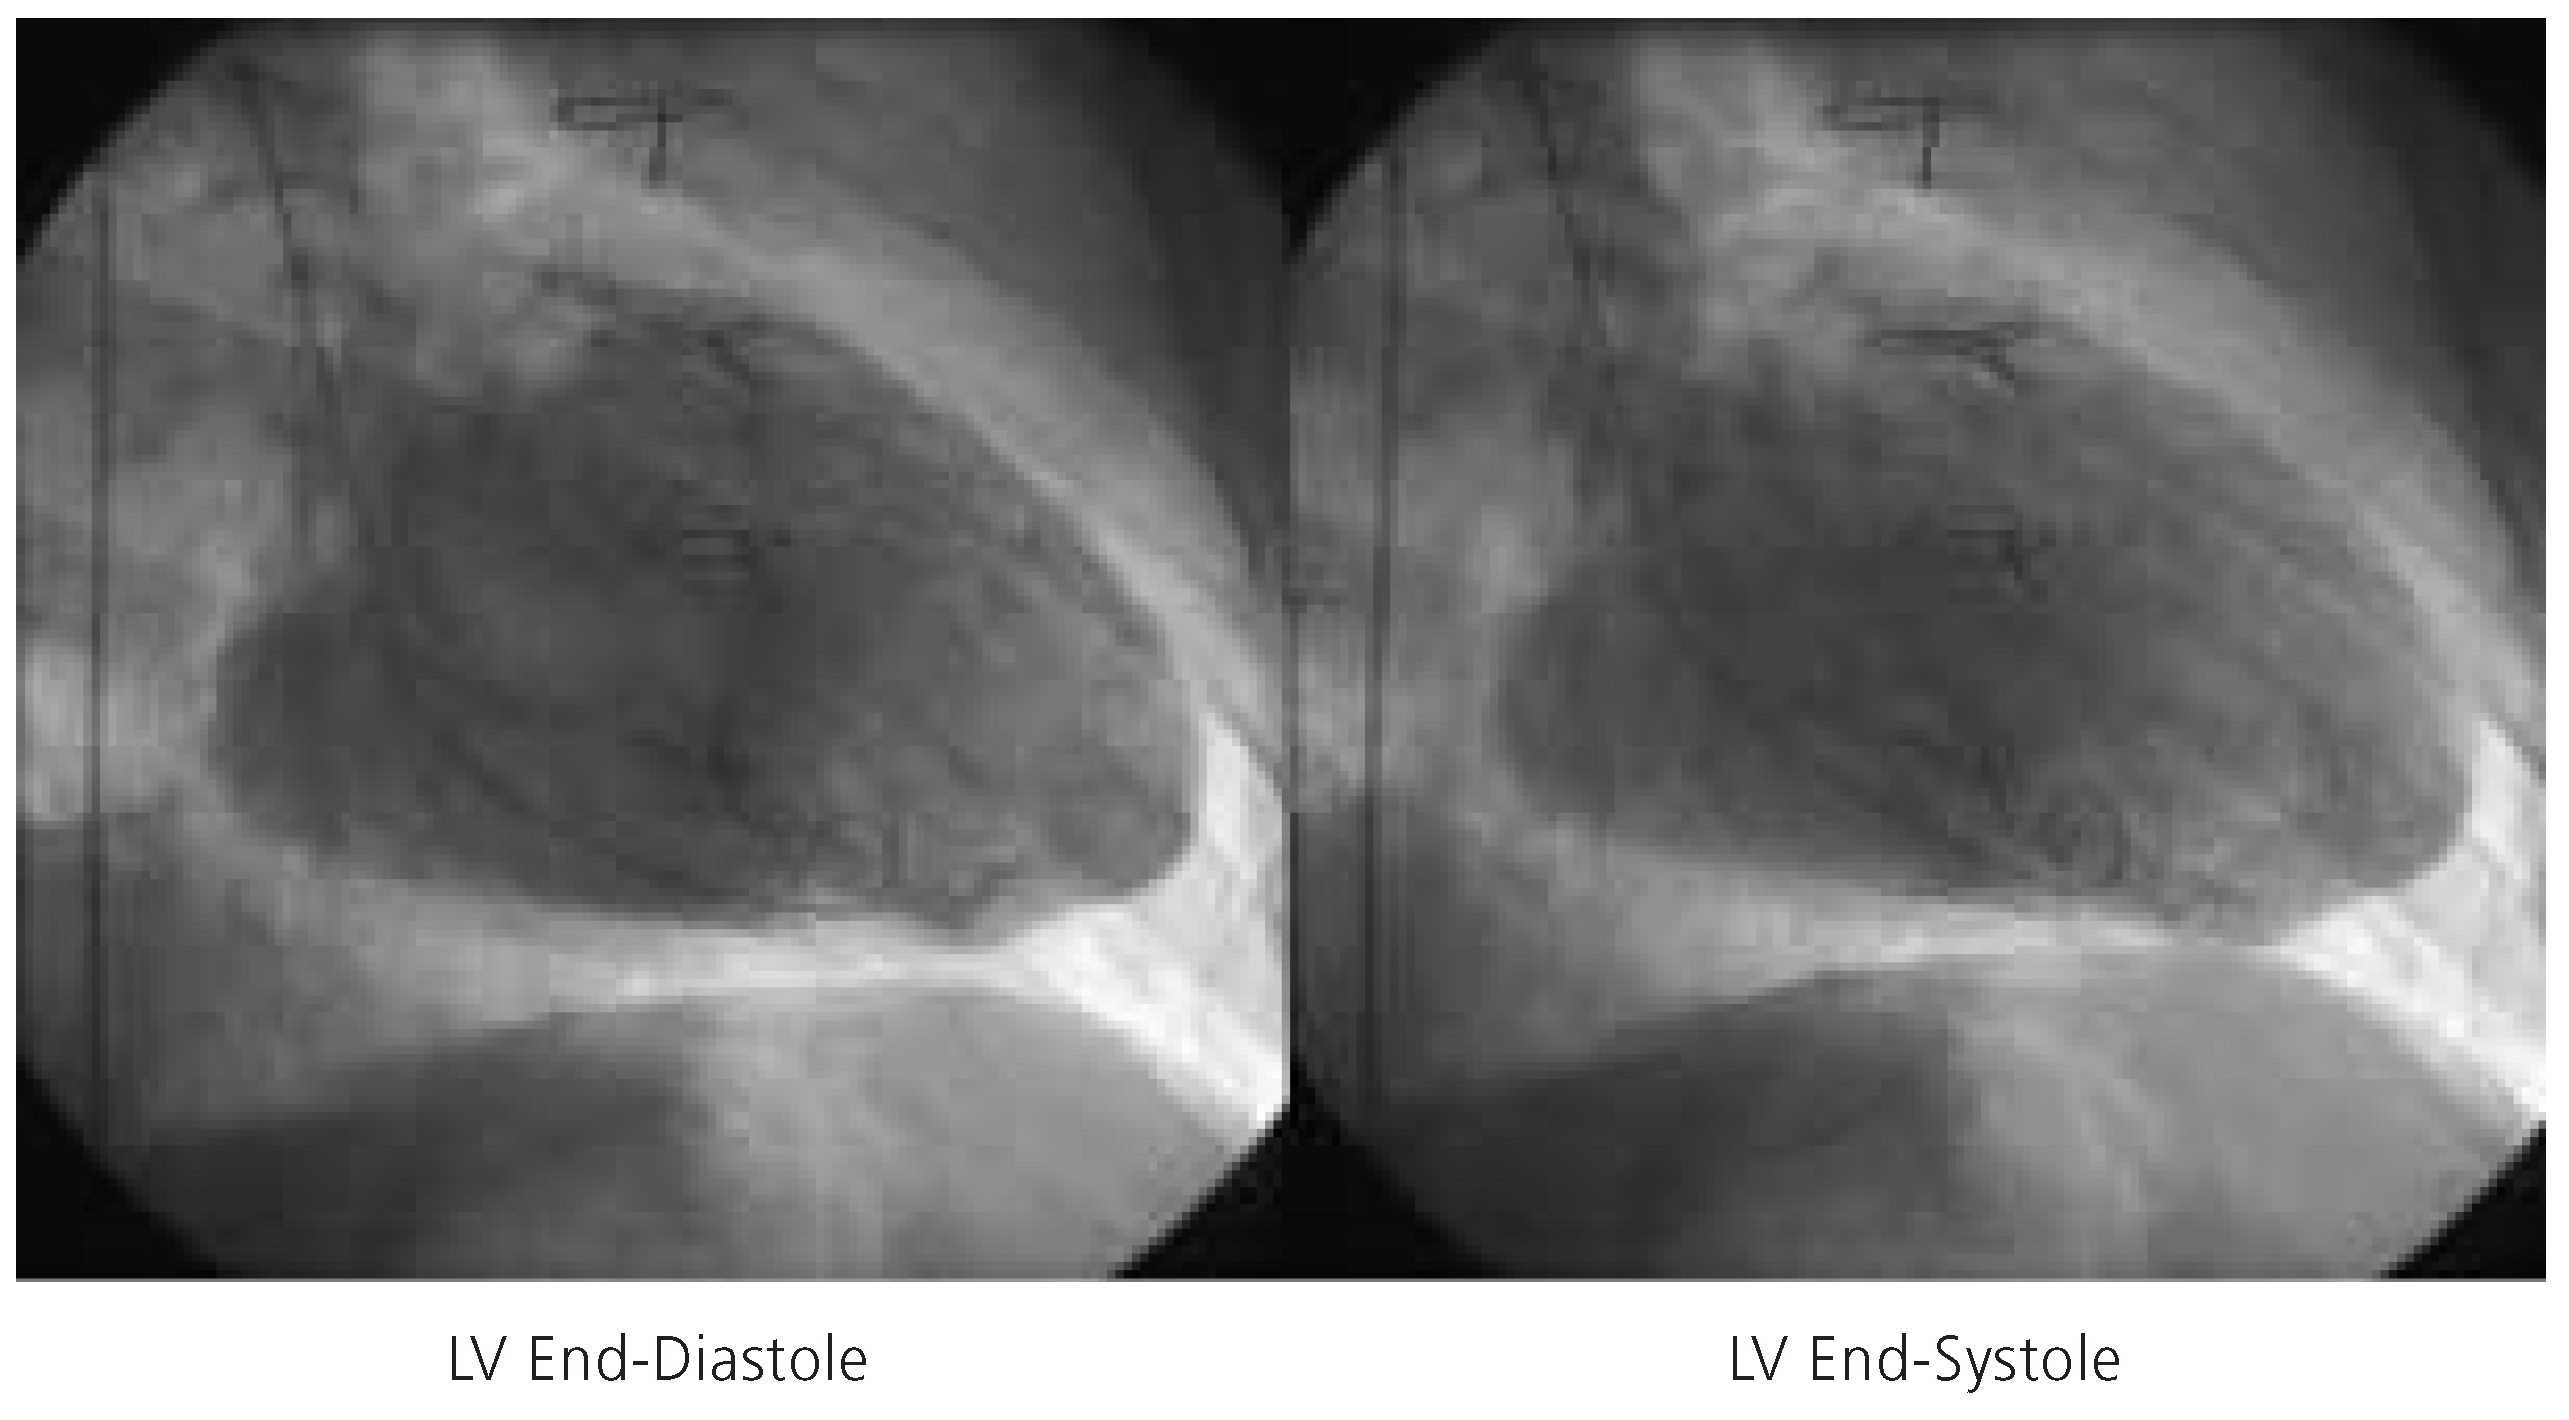

Left ventricular end-diastolic frame (left) and left ventricular end-systolic frame (right) indicative of severely diminished left ventricular function (LVEF = 15%). LV = left ventricle.

A 64-year-old man with a long history of coronary artery disease was admitted due to crescendo angina pectoris and dyspnea on exertion. He had suffered an anterior and inferior myocardial infarction in 1986 and 1990, respectively, and undergone coronary artery bypass grafting with a left internal mammary artery to the left anterior descending coronary artery, and two saphenous vein grafts to the right coronary artery and the second marginal branch of the circumflex coronary artery in 1990. Cardiac catheterisation during this admission revealed native three vessel coronary artery disease with occlusion of the left anterior descending artery in the mid portion, three complex and high grade stenoses of the left circumflex artery, and proximal occlusion of the right coronary artery. The left internal mammary artery graft to the distal left anterior descending artery was patent, whereas the saphenous vein graft to the marginal branch of the left circumflex artery was occluded and the saphenous vein graft to the right coronary artery had been stented earlier for a high grade stenosis at the distal anastomosis. Left ventriculography revealed a severely diminished left ventricular function with an ejection fraction of 15% with dyskinesia of the entire anterolateral wall, akinesia of the inferior wall, and severe hypokinesia of the posterior and lateral wall (fig. 3). The left ventricular enddiastolic pressure measured 38 mm Hg.